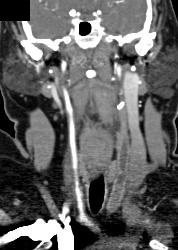

Carotid Artery Stenosis